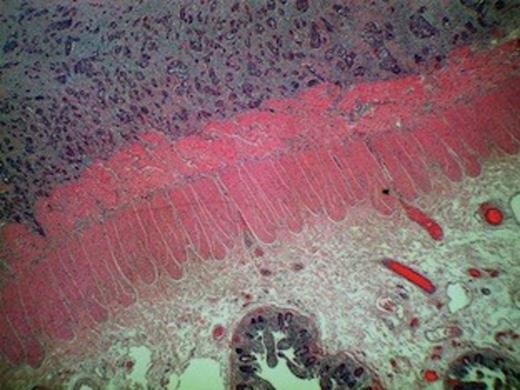

Keratin pearls confirming squamous cell carcinoma metastasis in the tumour specimen

Despite an initial response to treatment, four months later, the patient presented with clinical picture suggestive of large bowel obstruction. An explorative laparotomy unveiled a large mass involving the terminal ileum and caecum along with dense adhesions of ileocaecal loops. A 4 cm nodule in the right lobe of liver was also discovered. The patient underwent right hemicolectomy with an end-to-end ileocolic anastomosis. The surgical specimen consisted of 21 and 15 cm length of small and large bowel, respectively. The central 10 cm of the bowel was of undeterminable nature due to its tortuous nature caused by innumerable adhesions. The mucosa was unremarkable except for focal oedema. Histological examination showed poorly-differentiated squamous cell carcinoma infiltrating serosa with prominent intravascular spread. The tumour was predominantly confined to the peritoneal fat and serosa with no obvious invasion of the muscularis, submucosal, and mucosal layers (Figure 1 and 2). The appearance was consistent with metastatic spread from primary anal lesion. Unfortunately, the patient did not recover and died from multiple organ failure on the fourth post-operative day.